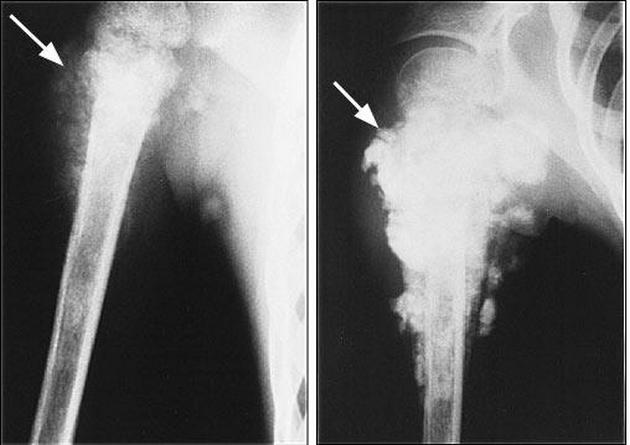

Опухоль может возникнуть в костях таза – это заболевание носит название «остеосаркома». Человек ощущает боль во всей тазовой области. Женщине при подозрении на такую болезнь стоит наблюдаться у онколога, предварительно диагностировав возможный диагноз при помощи МРТ или КТ.